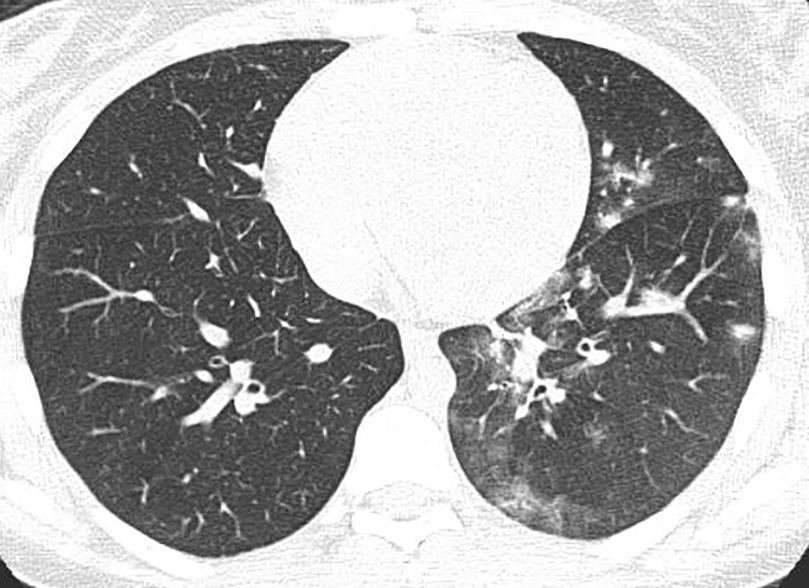

Acute Pediatric COVID-19: CT

21 Imaging of Covid 19 infection in children

3 Phases

Early: "Halo" sign

Local infection

Progressive: Diffuse GGO

Developed: Consolidation

Surr vasc congestion

Inflammation - adj alveoli

Alveoli fill with fluid/cells